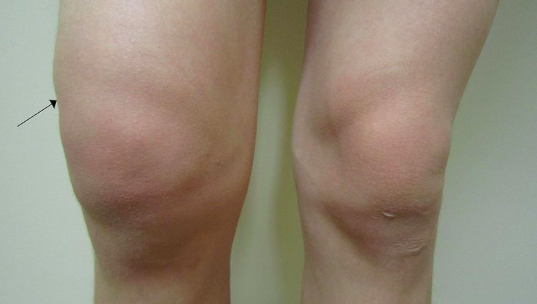

• Look for any redness, skin changes, swelling, temperature changes and compare with contralateral joint

• Check for any focal tenderness and joint effusions